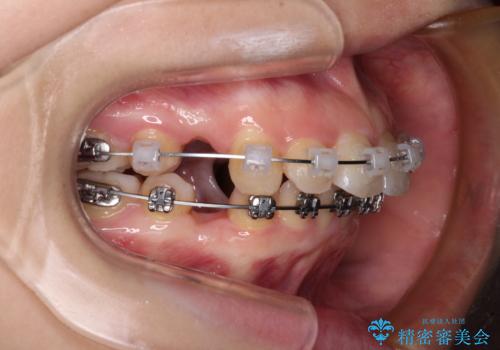

- メタルブラケット

舌の突出癖があり、前歯の移動量も多くなるため、治療期間は長くなると予想されましたが、13ヶ月という予定の半分程度の期間で終えることができました。

※写真にある上顎装置はメタルブラケットではありません。メーカー在庫都合などにより別の装置を使用しております。